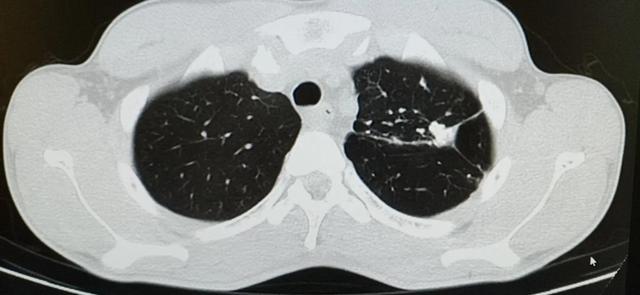

亚急性或慢性血行播散型肺结核

CT肺窗,两肺可见大小不一、密度不均、分布不均的粟粒及小结节影

(1)X线:病灶大小不一,可从粟粒样至直径 1cm 左右;密度不均,渗出增殖性病灶,密度较高,边缘较清楚,钙化灶密度更高,边缘锐利;分布不均,老的硬结钙化病灶大都位于肺尖和锁骨下,新的渗出增殖病灶大都位于下方。此即所谓“三不均匀”,与急性粟粒型肺结核的“三均匀”所见不同。少数病例的粟粒病灶融合,产生干酪样坏死,形成空洞和支气管播散,X线表现更多样而复杂。

(2)CT:在显示病灶分布、大小、密度方面较X线更加敏感和清楚,亦可显示细小的钙化灶及结节的融合情况。